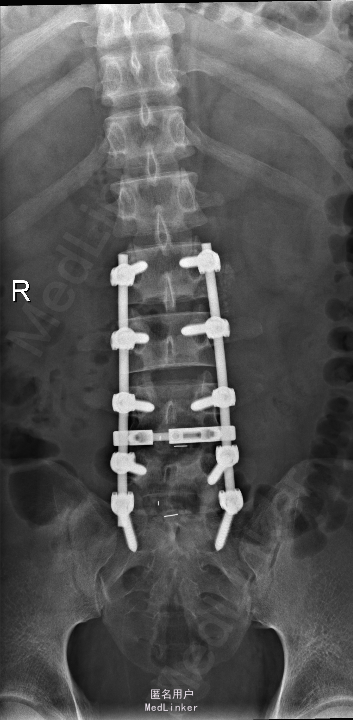

查体:腰部叩痛,腰部活动受限,左侧膝内侧、小腿外侧、内踝、足部感觉减退,右侧小腿、足背感觉减退,屈髋、伸膝、踝背伸肌肌力左侧4级,右侧4-5级,踇背伸、跖屈肌肌力左侧3-4级,右侧4级,双侧膝腱反射+,跟腱反射+,双侧巴氏征阴性,直腿抬高试验左侧40°阳性,右侧阴性。 辅助检查: X-ray:腰椎退行性变,多节段不稳 CT:腰椎间盘突出并椎管狭窄伴钙化,腰2-3,3-4,4-5,腰5骶1 MR:腰椎间盘突出并椎管狭窄,腰2-3,3-4,4-5,腰5骶1 上传受限无法全部上传,见谅

诊断:腰椎间盘突出症并椎管狭窄 处理: 1、完善相关辅助检查,明确诊断,有无手术指证; 2、完善手术评估,有无手术禁忌,手术风险及并发症; 3、在全麻下行腰椎后路多节段减压椎间植骨融合内固定术 4、腰2-3,腰3-4行开窗减压,腰4-5,腰5-骶1行椎间Cage植骨融合

随访: 1、应常规术后1个月、3个月、半年随访; 2、术后患者腰痛较前减轻,下肢麻木感觉较前好转,下肢活动较前有力,屈髋、伸膝、踝背伸肌肌力左侧4级,右侧4-5级,踇背伸、跖屈肌力左侧4级+,右侧4-5级,左侧肢体抬高试验阴性。 讨论: 1、多节段腰椎间盘突出,手术指证把握 2、责任节段的确立,以影像学间盘突出节段为依据,还是联系临床表现?还是术中探查为金标准? 3、多节段间盘突出,开窗髓核VS椎间植骨融合? 4、开窗髓核与椎间植骨融合相结合,如何确定融合节段与开窗节段? 5、多节段内固定,腰椎活动度影响,稳定与腰椎活动功能的平衡?